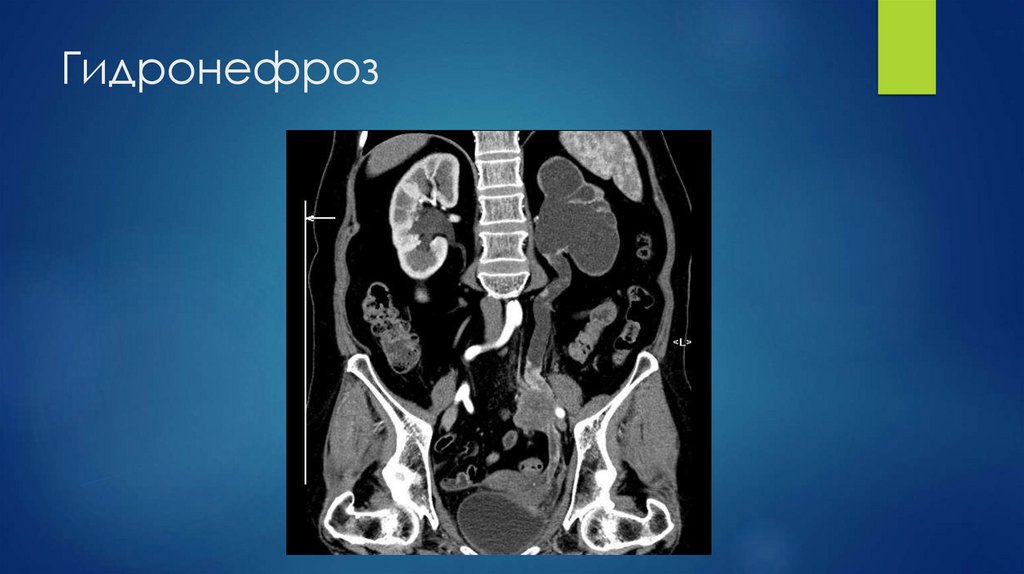

Гидронефроз

69. Гидронефроз